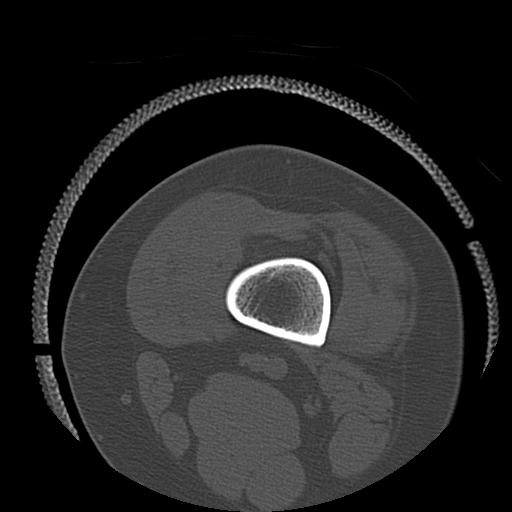

49554 3/13 膝 4R 3/16 4R 1/18 2R 78歳男性 膝蓋骨骨折